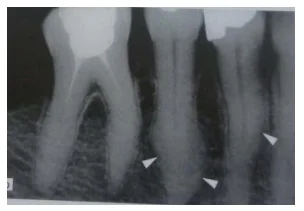

Anomalies du cément

Hypo- et aplasie du cément — Anomalie radiologique affectant surtout les dents temporaires antérieures, généralement avant l’âge de 3 ans.

Cémenticules — Petits noyaux calcifiés sphériques se développant dans le desmodonte, souvent au niveau des furcations molaires.

Hypercémentose — Atteint surtout les molaires mandibulaires, localisée au tiers apical, formant un bourrelet de cément acellulaire. Chez les dents jeunes, elle peut entraver l’éruption, provoquer des courbures radiculaires ou conduire à une ankylose. Les causes incluent des surcharges mécaniques, une inflammation périapicale ou des affections générales comme la maladie de Paget.